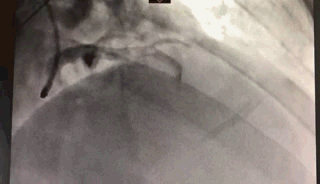

冠状动脉造影

上图)左冠状动脉没有闭塞。